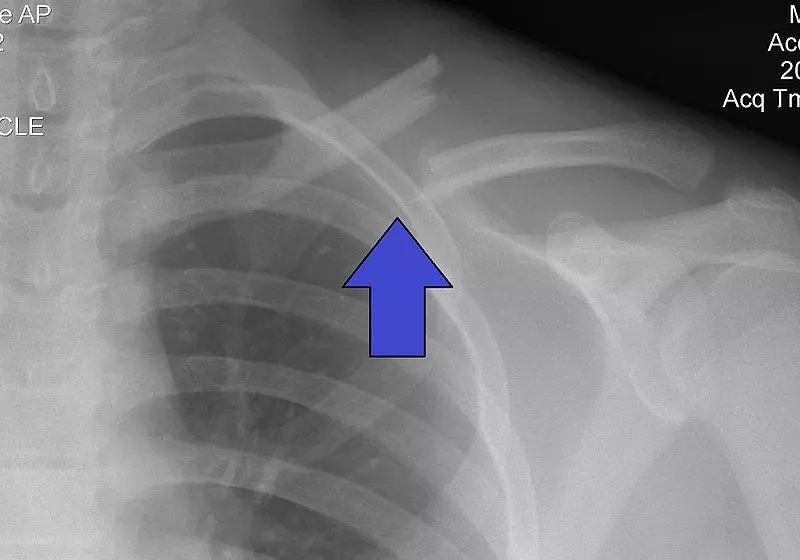

Calcific Supraspinatus Tendinitis

Calcific supraspinatus tendinitis occurs when macroscopic deposits of hydroxyapatite crystals accumulate in the tendon of the supraspinatus muscle. It presents with shoulder pain aggravated by flexion and abduction; as well as mechanical symptoms such as stiffness, snapping or catching sensations.

Diagnostic tests include X-rays (which reveal larger deposits) and ultrasound scans (to pick up smaller deposits that an x-ray may have missed). Treatment can include NSAIDs for pain management, shock wave therapies, physical therapy or surgery (rarely used).

Image - An X-ray of calcific supraspinatus tendinitis indicated by the red circle

Creative commons source by Emilios Pakos, Ioannis Gkiatas, Georgios Rakkas, Dimitrios Papadopoulos, Ioannis Gelalis, Marios Vekris and Anastasios Korompilias [CC BY-SA 4.0 (https://creativecommons.org/licenses/by-sa/4.0)]